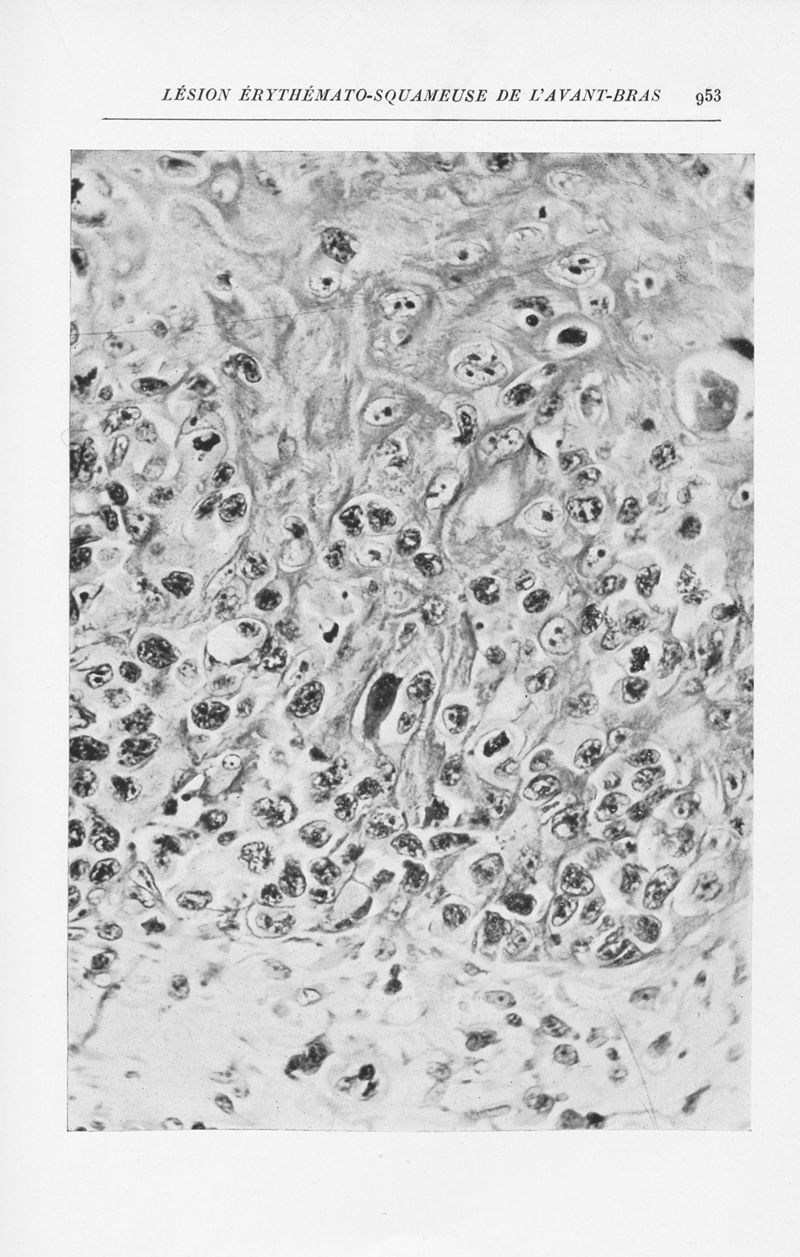

Annales de dermatologie et de syphiligraphie

7ème série, tome X. - Paris : Masson, 1939-1940.